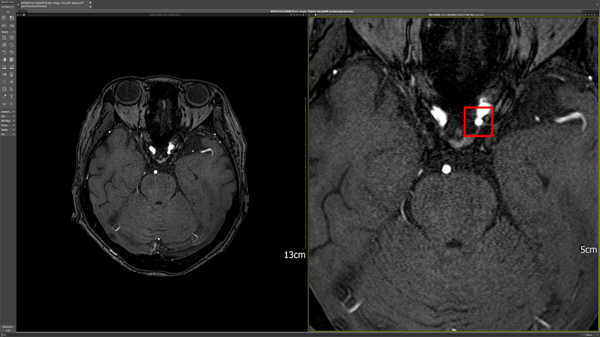

(서울=) 이복현 기자 = 국내 의료 인공지능 전문기업 딥노이드(대표 최우식)의 AI기반의 뇌동맥류 검출 진단보조 솔루션 ‘DEEP:NEURO(딥뉴로)’가 건강보험 비급여로 의료기관에서 사용을 시작했다.

딥뉴로는 뇌 MRA 영상에서 AI를 활용해 뇌동맥류를 검출해 의료진의 진단을 보조하는 솔루션이다. 뇌동맥류에 대한 일관된 결과를 제공하며 영상판독 편의성과 정확도를 높임으로써 의료진의 빠른 대응과 치료가 필요한 뇌혈관질환의 골든타임을 지킬 수 있을 것으로 예상한다.